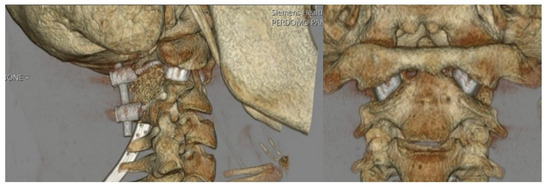

3.1. Preoperative Planning and 3DPI Design

3.2. Surgical Approach

4. Results